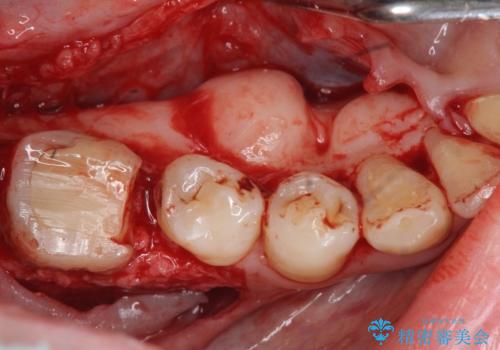

加えて、舌の邪魔になっている骨隆起や根尖病変といった問題を歯周外科・精密根管治療を行い、しっかりとスペースを確保したのちセラミッククラウンを作製していきます。

外科処置の注意事項(リスク・副作用など)

- 外科手術のため、術後に出血、痛みや腫れ、違和感を伴います

- 口腔内の状態によっては適応できないことがあります